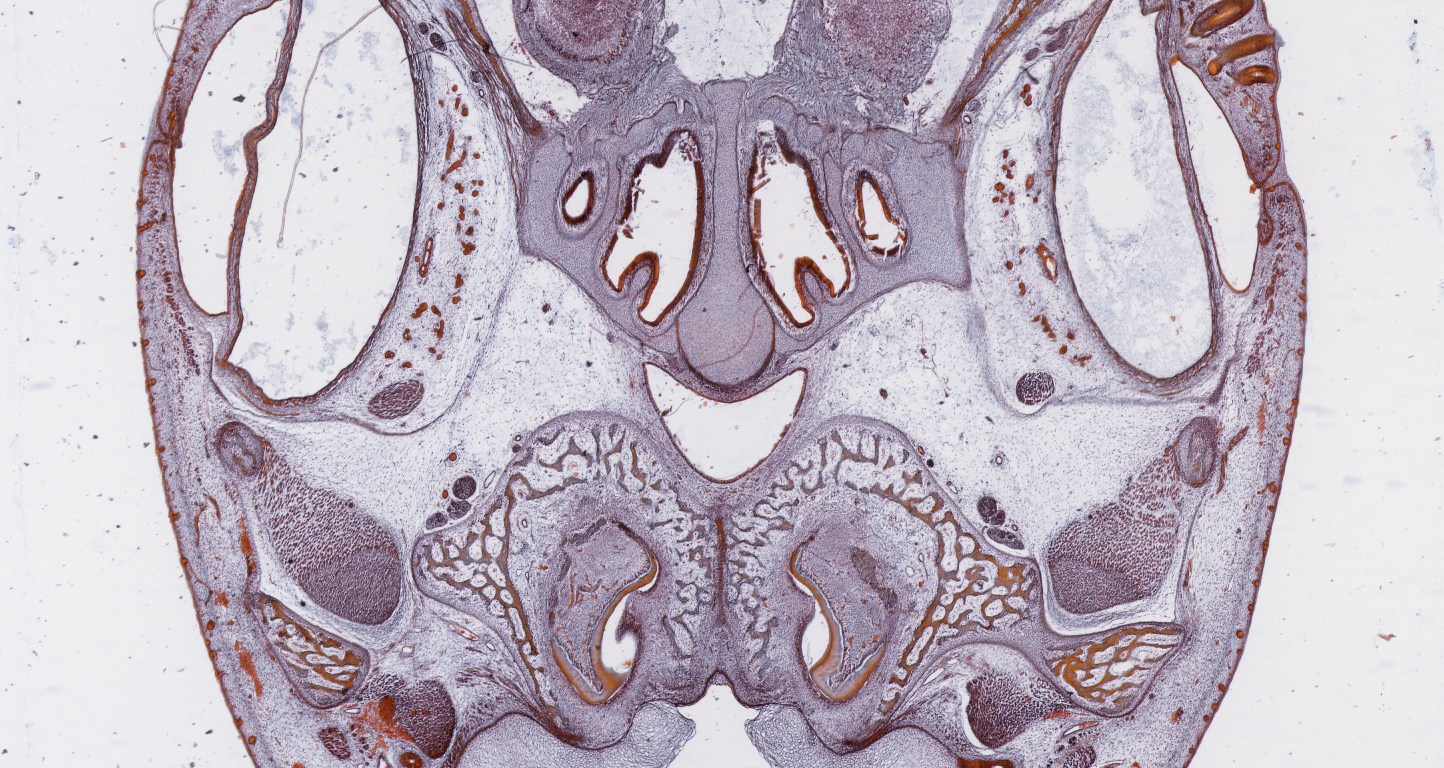

Images Membranous Bone Development in Fetal Skull From SMC collection. Membranous Bone in Fetal Skull (TM: 2.5x, picture taken with a Nikon Coolscan V Slide scanner from a damaged slide) Share this: Email a link to a friend (Opens in new window) Email Share on X (Opens in new window) X Share on Facebook (Opens in new window) Facebook Like Loading...